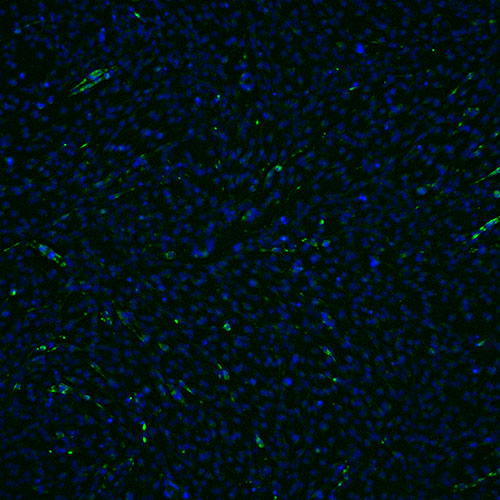

Technical excellence in our preclinical CRO Services

- Aging Model for example

Health Muscle Cells

Blue: nucleus

Green: myotube

Senescent Muscle Cells